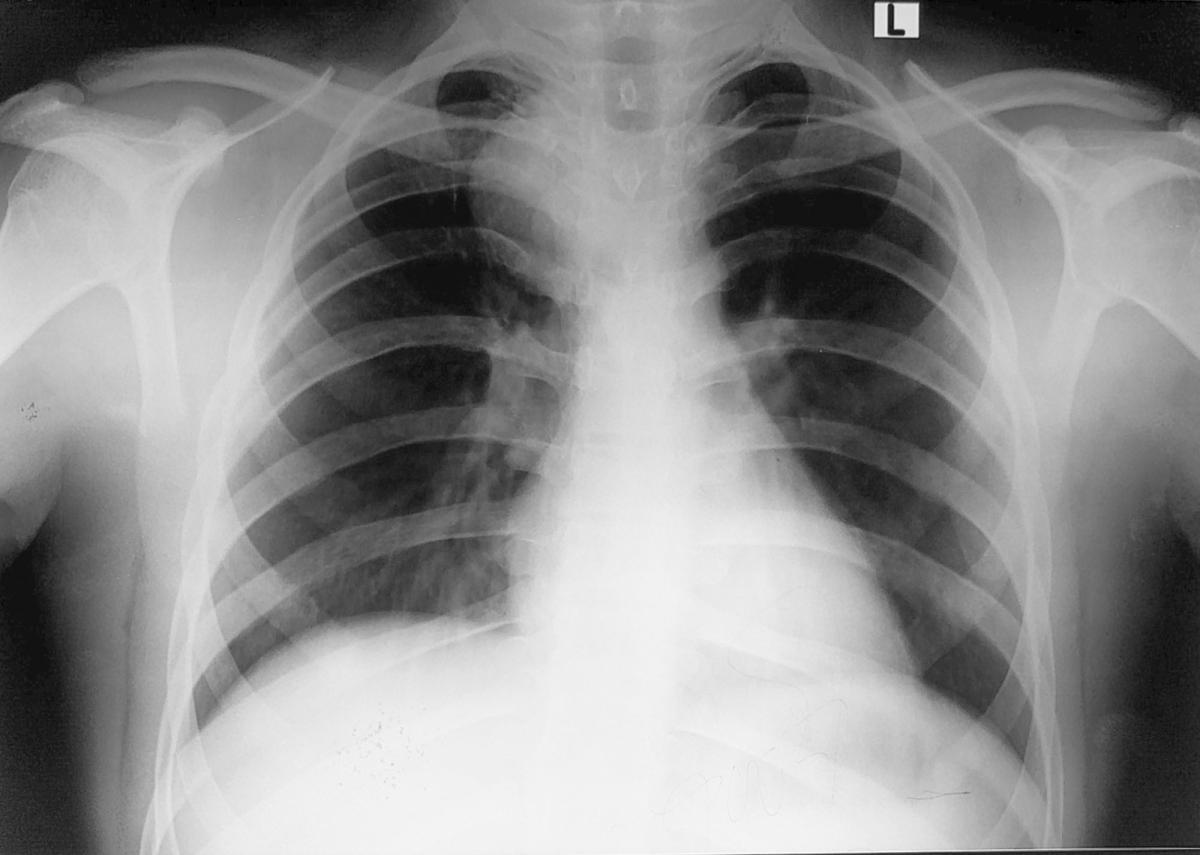

Figure 7. Chest x-ray showing a fully expanded lung with no residual opacity.

The patient was diagnosed as having a bronchogenic cyst. The authors decided to treat the patient surgically. The patient underwent a right-sided posterolateral thoracotomy via the fifth intercostal space. A round, smooth, uniform, soft, cystic mass in the posterior mediastinum was found, measuring 3.5 x 2 x 3 cm. The mass was extrapleural, adherent to the esophagus and trachea posteromedially, to the apical lobe of the lung anterolaterally, and to the azygous vein inferiorly. The pleural layer was peeled off the mass. The mass was dissected free from surrounding structures and was found to be growing from the right main bronchus from a pedicle. The pedicle was found to be cartilaginous on palpation. The pedicle was ligated, and the mass was excised. The pleura was closed back with Vicryl sutures. The chest cavity was washed with normal saline and checked for air leak. Two chest tubes were placed: posteroapically and posterobasally. Routine chest closure was performed. The patient was extubated and subsequently shifted to the ward in stable condition. Postoperatively, chest x-ray showed a fully expanded lung with no residual opacity. On the second postoperative day, the chest tubes were removed and the patient was discharged.